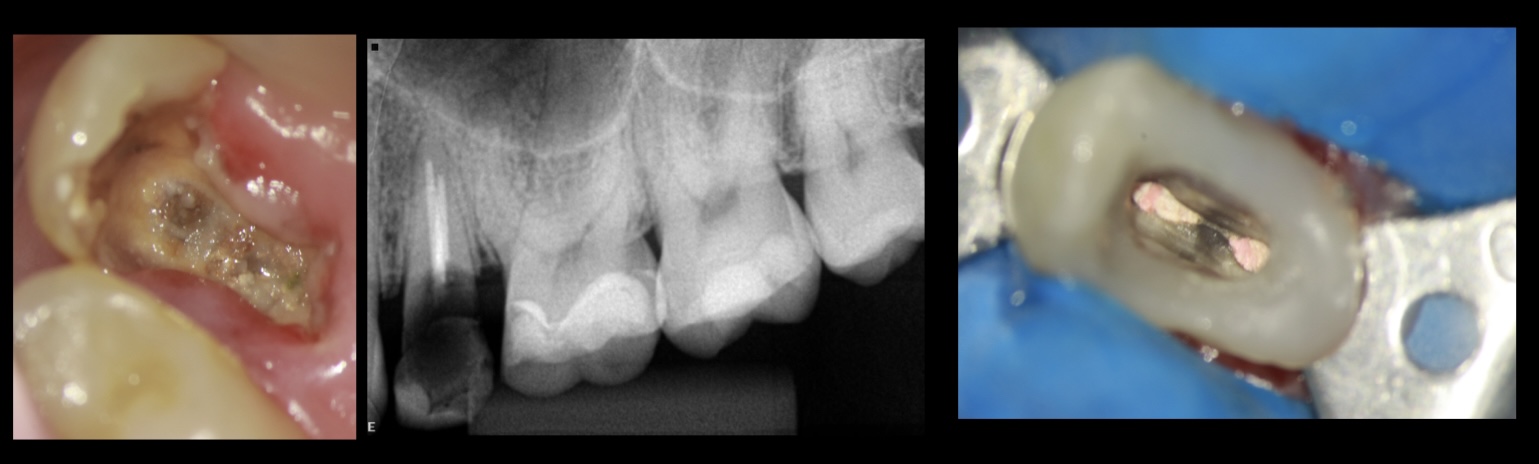

Partimos do conceito de DME (Deep Margin Elevation) de Pascal Magne e Roberto Spreafico (2012) que em seu artigo descrevem que a ideia não é somente elevar as margens subgengivais para auxiliar na endodontia. A ideia também é deixar o preparo supragengival para facilitar o preparo para onlay ou coroa protética.

Em caso de margens subgengivais em dentes, que possuem dentes adjacentes, para erguer suas paredes e ajudar na reconstrução. Você pode usar o mesmo protocolo usando está resina citada no artigo e poderá inclusive por um grampo de isolamento em cima deste mesmo dente (figura 4, 5, 6 e 7).